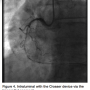

A 62-year-old male with history of hypertension, diabetes, and hypercholesterolemia underwent diagnostic angiography via the right radial artery. He was found to have a CTO of the RCA. The right radial was prepped and we accessed with a 6 Fr Terumo Glide sheath (Somerset, NJ). The sheath was upsized to a 7 Fr sheath. An AL .75 guide wire was used to engage the coronary system. Using the Flowcardia Crosser device and a cougar wire, we were

able to cross the CTO and achieve luminal entry. Following the removal of the Crosser, the cougar was advanced into the PDA. We used a 2.0 x 40 mm Apex to predilate the lesion. We then placed a Promus (Boston Scientific Corp., Natick, MA) 3.0 x 28 mm and a 3.0 x 15 mm stent. We post dilated with a 3.25 Quantum Maverick balloon. At this point, we administered 200 mcg intracoronary nitroglycerin and revealed TIMI-3 flow, with no perforation or embolization. After removal of wire and guide, a TR Band (Terumo) was applied.